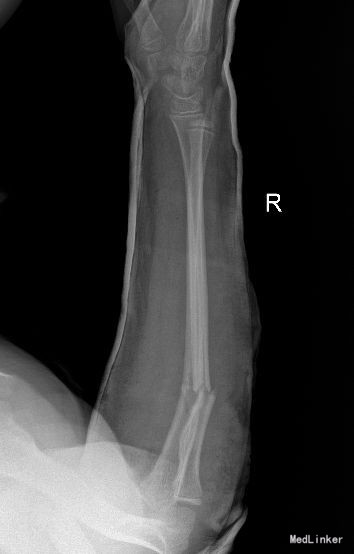

主 诉:摔倒致右前臂疼痛、畸形、活动受限14天。 现病史:14天前,患者在玩耍时摔倒,右前臂先触地,即感右前臂疼痛、畸形、活动受限,受伤当时无头晕头疼,无恶心呕吐等不适。被家人送入我院,行右前臂正侧位X线检查示“右尺桡骨骨折”,手法复位并石膏托固定后复查示“骨折断端对位对线尚可”,嘱患者定期随诊。今患者来我院复查,行右前臂正侧位片检查示“骨折断端对位对线欠佳,桡骨远折端向背侧成角”,患者家属要求住院手术治疗,门诊经检查后以“右尺桡骨骨折”位诊断收入我科。发病以来,神志清楚,精神尚可,无恶寒发热,饮食、大小便正常,睡眠可,体重无明显变化。

专科检查:步入病房。右前臂石膏托固定,去除石膏托后右前臂未见明显肿胀,中段压痛阳性,纵向叩击痛阳性,可触及骨擦感,因前臂疼痛致右肘、腕关节活动受限,肘后三角正常,腕关节、肘关节压痛阴性,右前臂痛触觉较左侧未见明显异常,右侧桡动脉搏动可扪及,末梢血液循环可。

西医诊断:右尺桡骨骨折 治疗:全麻下行“右尺骨骨折切复内固定术”